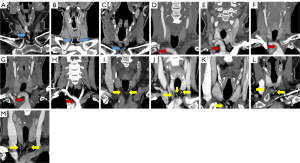

We collected demographic characteristics, clinicopathological data on primary disease, comorbidities, and treatment status for all participants. The reasons for OST in both groups were summarized through face-to-face interviews with all the relevant surgical operators. Using preoperative CECT/CTV images, two radiologists independently analyzed the morphological relationships of following targets: (I) the AJV; (II) IA; (III) ITVP, including the inferior thyroid vein (ITV) or the lowest thyroid artery; and (IV) the thyroid isthmus. According to the OST procedure (from skin to trachea), the superficial relationship of the AJV was first analyzed for comparisons. Second, the representative radiographic and clinical evidence of the IAs was recorded. Third, the lower edges of thyroid isthmus were measured for possible interruptions of tracheal exposure. Finally, the presence of the ITVs, or the lowest thyroid arteries, which mainly run between the pre-tracheal fascia and the anterior parts of the trachea, were determined. We further classified the pre-tracheal AJVs as single-branch, double-branch, or multi-branch types (Figure 1). According to Sung et al.’s study (12), the IAs were categorized by their morphological characteristics as (I) the low-bifurcation type (the level of the superior border of the IA bifurcation crosses the tracheal anterior from the suprasternal notch at <2 cm); (II) high-bifurcation type (the level of the superior border of the IA bifurcation crosses the tracheal anterior from the suprasternal notch at ≥2 cm); (III) high-platform type (or high-lying IA, in which the upper edge of the platform IA crosses the tracheal anterior midline from the suprasternal notch ≥2 cm); (IV) low-platform type (namely low-lying IA, in which the upper edge of the platform IA passes through the tracheal anterior midline from the suprasternal notch at <2 cm); and (V) variant type. Among these types, the low-bifurcation type was considered the normal IA type, with sufficient space for a safe and routine OST procedure. Admittedly, due to possibly unrecognized discrepancies in CECT, ITVs and the lowest thyroid arteries were combined into a single category of (ITVPs) for ease of analysis. We further classified them based on the presence or absence of trunks (independent or common trunk type) and communicating branches (with or without branches) (Figure 1). For quantitative clinical references, the maximum calibers of these three target vessels, and their shortest horizontal distances towards both skins and the anterior walls of 1st–5th tracheal cartilage rings were radiographically measured in both groups.

In terms of radiographic parameters, AJVs were not visible in the pre-tracheal region in 2 (2/201, 1%) patients. The distribution of classification among the remaining patients (n=199) was as follows: (I) 10.4% had the single-branch type (21/199); (II) 80.1% had the double-branch type; and (III) 8.5% had the multibranch type. There was no statistically significant difference in the AJVs types between the older adult and the non-older adult groups (P>0.05; Table 2). The median shortest distance to the midline of the lower neck was 3.6 mm (range, 0–15.3 mm). Moreover, the CECT/CTV parameters for the single-branch type only were compared, and there was a significant difference in the maximum pipe caliber (P<0.05, Table 3). In addition, the proportion of double-branch type in the non-older adult group is slightly lower than that in the older adult counterpart. The median distance between the double branches of AJVs in the non-older adult and the older adult groups was 12.8±6.1 mm (range, 2.4–28.7 mm) and 14.3±6.0 mm (range, 3.0–31.4 mm), respectively, while the median of the shortest distance to the midline of the neck in the two groups was 3.0 mm (range, 0–14.1 mm) and 3.5 mm (range, 0–15.3 mm), respectively, indicating a high probability of encountering AJVs or their branches in both groups during OSTs. Additionally, by means of univariate correlation analysis, we found that comorbidities were not statistically associated with our AJV classification (P=0.701) in the overall cohort (201 cases). However, after covariates (diabetes and hypertension) were incorporated, the multivariate analysis showed a significant difference in this regard (P<0.01; Table S1), suggesting that these two comorbidities influence the variations in the AJVs. As shown in Table 2, the majority of cases in the older adult and non-older adult groups had a low-bifurcation IAs (104/201, 51.7%), while other variant types were less common. There were strong correlations found between age and IA types (P=0.004) with a much higher proportion of platform IAs in the older adult group (47/127, 37%) than in the non-older adult group (10/74, 13.6%), indicating an age-related change in IA locations in the pre-tracheal region. A further examination of the overall cohort revealed that the median age of the five IA types were 66.5 (range, 12–87), 58.0 (range, 21–84), 67.0 (range, 33–87), 69.0 (range, 28–84) and 65.0 (range, 50–73) years. within whom the high-platform one (directly interfering with the OST) had the highest median age (69.0 years, P=0.042). Regarding tracheostomy, the tracheal-to-IA and skin-to-IA distances for the first four IA types are shown in Table 3. In the multivariate analysis, diabetes and hypertension were also found to be statistically associated with pre-tracheal IA classifications (P=0.008; Table S1).

As for the ITVPs, only 2 patients did not have ITVPs on CECT/CTV; meanwhile, there were 77 (77/199, 38.7%) patients with a common trunk, and 32 (32/72, 44.4%) with large-diameter (≥2 mm) communicating branches (Figure 1). Univariate analysis of variance indicated that in terms of ITVPs, whether grouped by trunk (P=0.623) or communicating branch (P=0.117) types, the difference between the older adult and the non-older adult group did not reach statistical significance (Table 2). However, Significant differences could be discerned in the shortest distance to the trachea of the independent trunk type by comparing the CECT/CTV parameters between these two groups (P<0.05, Table 3). Among these patients, 60 (60/74, 81.1%) in the non-older adult group and 45 (36.0%, 45/125) in the older adult group had one or more branches of the ITVP running through the lower border of the thyroid isthmus.

According to our intraoperative data, possible high-platform IAs were found or exposed in 20 (20/127, 15.7%) cases in the older adult group and 7 (7/74, 9.5%) cases in the non-older adult group. Owing to vascular anatomical variations of the IA, we detected prominent vascular pulsations in the cervical tracheotomy field during the physical examination performed as part of the tracheotomy procedure (Videos S1,S2). Thyroid-level tracheotomy (i.e., thyroid anatomy and higher-than-usual tracheal incision) was applied to ensure the safety of these patients. In addition, we compared the intraoperative exposure of the pre-tracheal vessels in the older adult patient group, which corroborated the image findings of the CECT/CTV analysis (Table 4 and Figure 2). The types of AJV, IA, and ITVP communicating branch were related to the location of the tracheal incision in the older adult group (rn=0.28, rn=0.59, and rn=0.267, all P<0.01; Table 4 and Tables S3,S4). All the single-branch and multi-branch AJVs in both groups were exposed in the second to fourth tracheal cartilage region, namely the so-called the OSTs’ common zone.